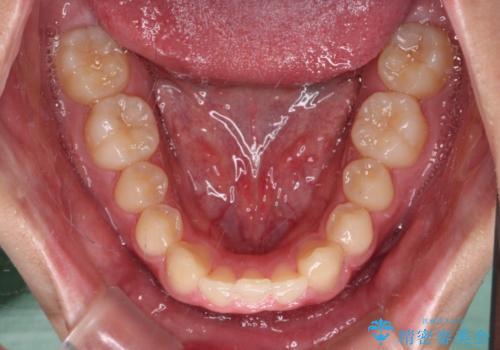

下顎前歯が一本欠損しており、下顎の歯列が小さいため、ディープバイトになりやすい状態でした。

傾斜しいている大臼歯を立ち上げながら、下顎歯列を上顎に対して前方位となるように工夫し、デコボコを解消した上でディープバイトも改善することができました。